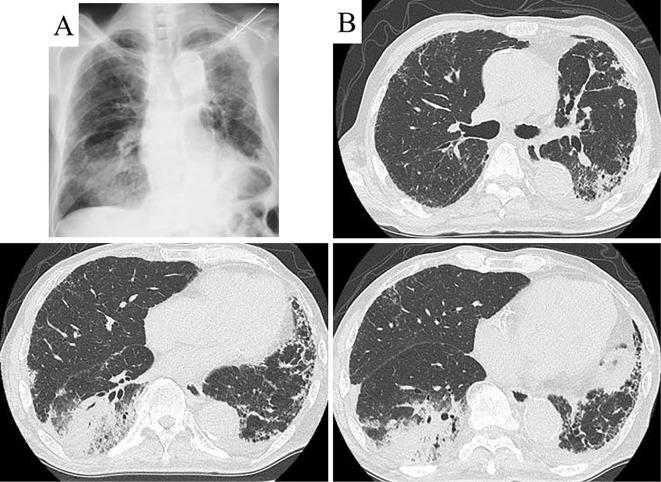

A 78-year-old man with a history of pancreatic carcinoma underwent chest computed tomography (CT), which revealed a slowly enlarging consolidation in the right lower lobe. Forceps and percutaneous CT-guided lung biopsies showed no evidence of malignancy; therefore, organizing pneumonia was suspected. However, the patient's serum carbohydrate antigen 19-9 levels increased monthly, raising concerns about malignant lesions. A transbronchial cryobiopsy (TBCB) was performed to confirm the diagnosis of pulmonary metastasis of the pancreatic carcinoma. Pulmonary metastasis is an important differential diagnosis when chest CT shows consolidation, mimicking organized pneumonia. In addition, a TBCB can be a useful diagnostic tool for detecting lepidic growth patterns.

一名有胰腺癌病史的78岁男性接受了胸部计算机断层扫描(CT),结果显示右下叶有一个逐渐增大的实变影。钳取活检和经皮CT引导下肺活检均未发现恶性证据;因此,怀疑为机化性肺炎。然而,患者的血清糖类抗原19-9水平每月都在升高,这引发了对恶性病变的担忧。为确诊胰腺癌肺转移,进行了经支气管冷冻活检(TBCB)。当胸部CT显示实变影,类似机化性肺炎时,肺转移是一个重要的鉴别诊断。此外,TBCB对于检测鳞屑样生长模式可能是一种有用的诊断工具。